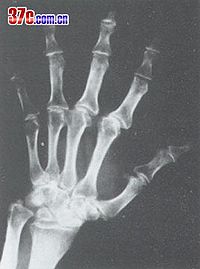

影像学表现

本病是在骨发育过程中发生的全身性、多发灶性、软骨坏死性疾病,造成的骨关节损害将持续终身,X

线征象归纳如下:

1.干骺端边缘模糊或凹凸不平,呈波浪状以至锯齿状。如病变继续发展,指骨端不整齐的边缘可呈碎裂现象。此时,关节无明显变形。

2.以骨骺与骨干开始融合为特征。骨骺自中央部分开始融合,渐扩展到边缘,骨骺本身亦有破坏、分节、不整等现象,也可能完全被吸收。干骺端可呈杯口状凹陷,骨髓嵌入其中而早期愈合,停止发育。

3.干骺完全融合,骨的纵向发育停止,病骨变短变粗。因为各干骺的融合迟早不同,以致各指骨可呈现长短不齐,骨端宽大变形,使关节粗大。

4.如干骺端愈合以后的青年发病,临床症状多见且严重。关节相对骨端都有损害,可影响整个关节,表现为大骨节畸形,可伴有短骨干。

5.大骨节病所见的系列征象都是软骨坏死后的修复和继发变化。只有经过修复组织特别是骨的改变塑型,病变才能发展到消退、稳定或发生畸形。

由于病人发病年龄、受累部位、病变发展阶段不同,X线有不同表现。原苏联与国学者曾主要依据于部X线改变将本病分为以下几型。

X线表现

⑴、干骼型:以干骼端改变为主,包括临时钙化带变薄、模糊、中断、消失,干骼端出现凹陷、硬化等。干骺型发生于学龄前及学龄儿童,反映骺板软骨坏死后的继发变化,代表大骨节病较早的损害,临床症状多为阴性或非常轻微。干骺型的X线变化除很明显的硬化在非病区儿童中较少见外,其他征象均可在非病区儿童中出现。因而在同一地区没有发现Ⅰ度以上典型病例的情况下,不宜仅凭某几点干骺端X线改变就诊断为本病。前面谈过的日本发现的所谓大骨节病,就是由于没有充分注意到这一点。⑵、干骺骨骺型:除上述干骼端变化外,骨骺也有变化,如骨骺常呈锥状或其他变形,嵌入凹陷的干骺端等。此型多发生于学龄及青春期,反映骺板软骨的一部分发生全层坏死,其干骺侧和骺核侧同时有生长障碍和骨质变化,局部骺板早期穿通化骨。这是干骺型的进一步发展。

⑶、骨端型:以骨端改变为主,包括骨性关节面模糊不整、变薄、中断、凹陷变形、硬化、甚至碎裂等改变。多发生于学龄儿童至青春期以后年龄段,反映关节软骨深层坏死继发的骨质改变。骨端的变化发展较慢,合并其他关节损害多。骨端出现变化的诊断意义比干骺端的变化更重要,更具有特异性。

⑷、骨关节型:见于骺线闭合、骺板软骨消失之后,包括骨关节面的严重破坏、凹凸不平、增生硬化、骨刺形成、骨质碎裂、囊性变、骨端粗大畸形等改变。常累及多关节,X线所见类似退行性(增生性)关节病,是本病的晚期表现。